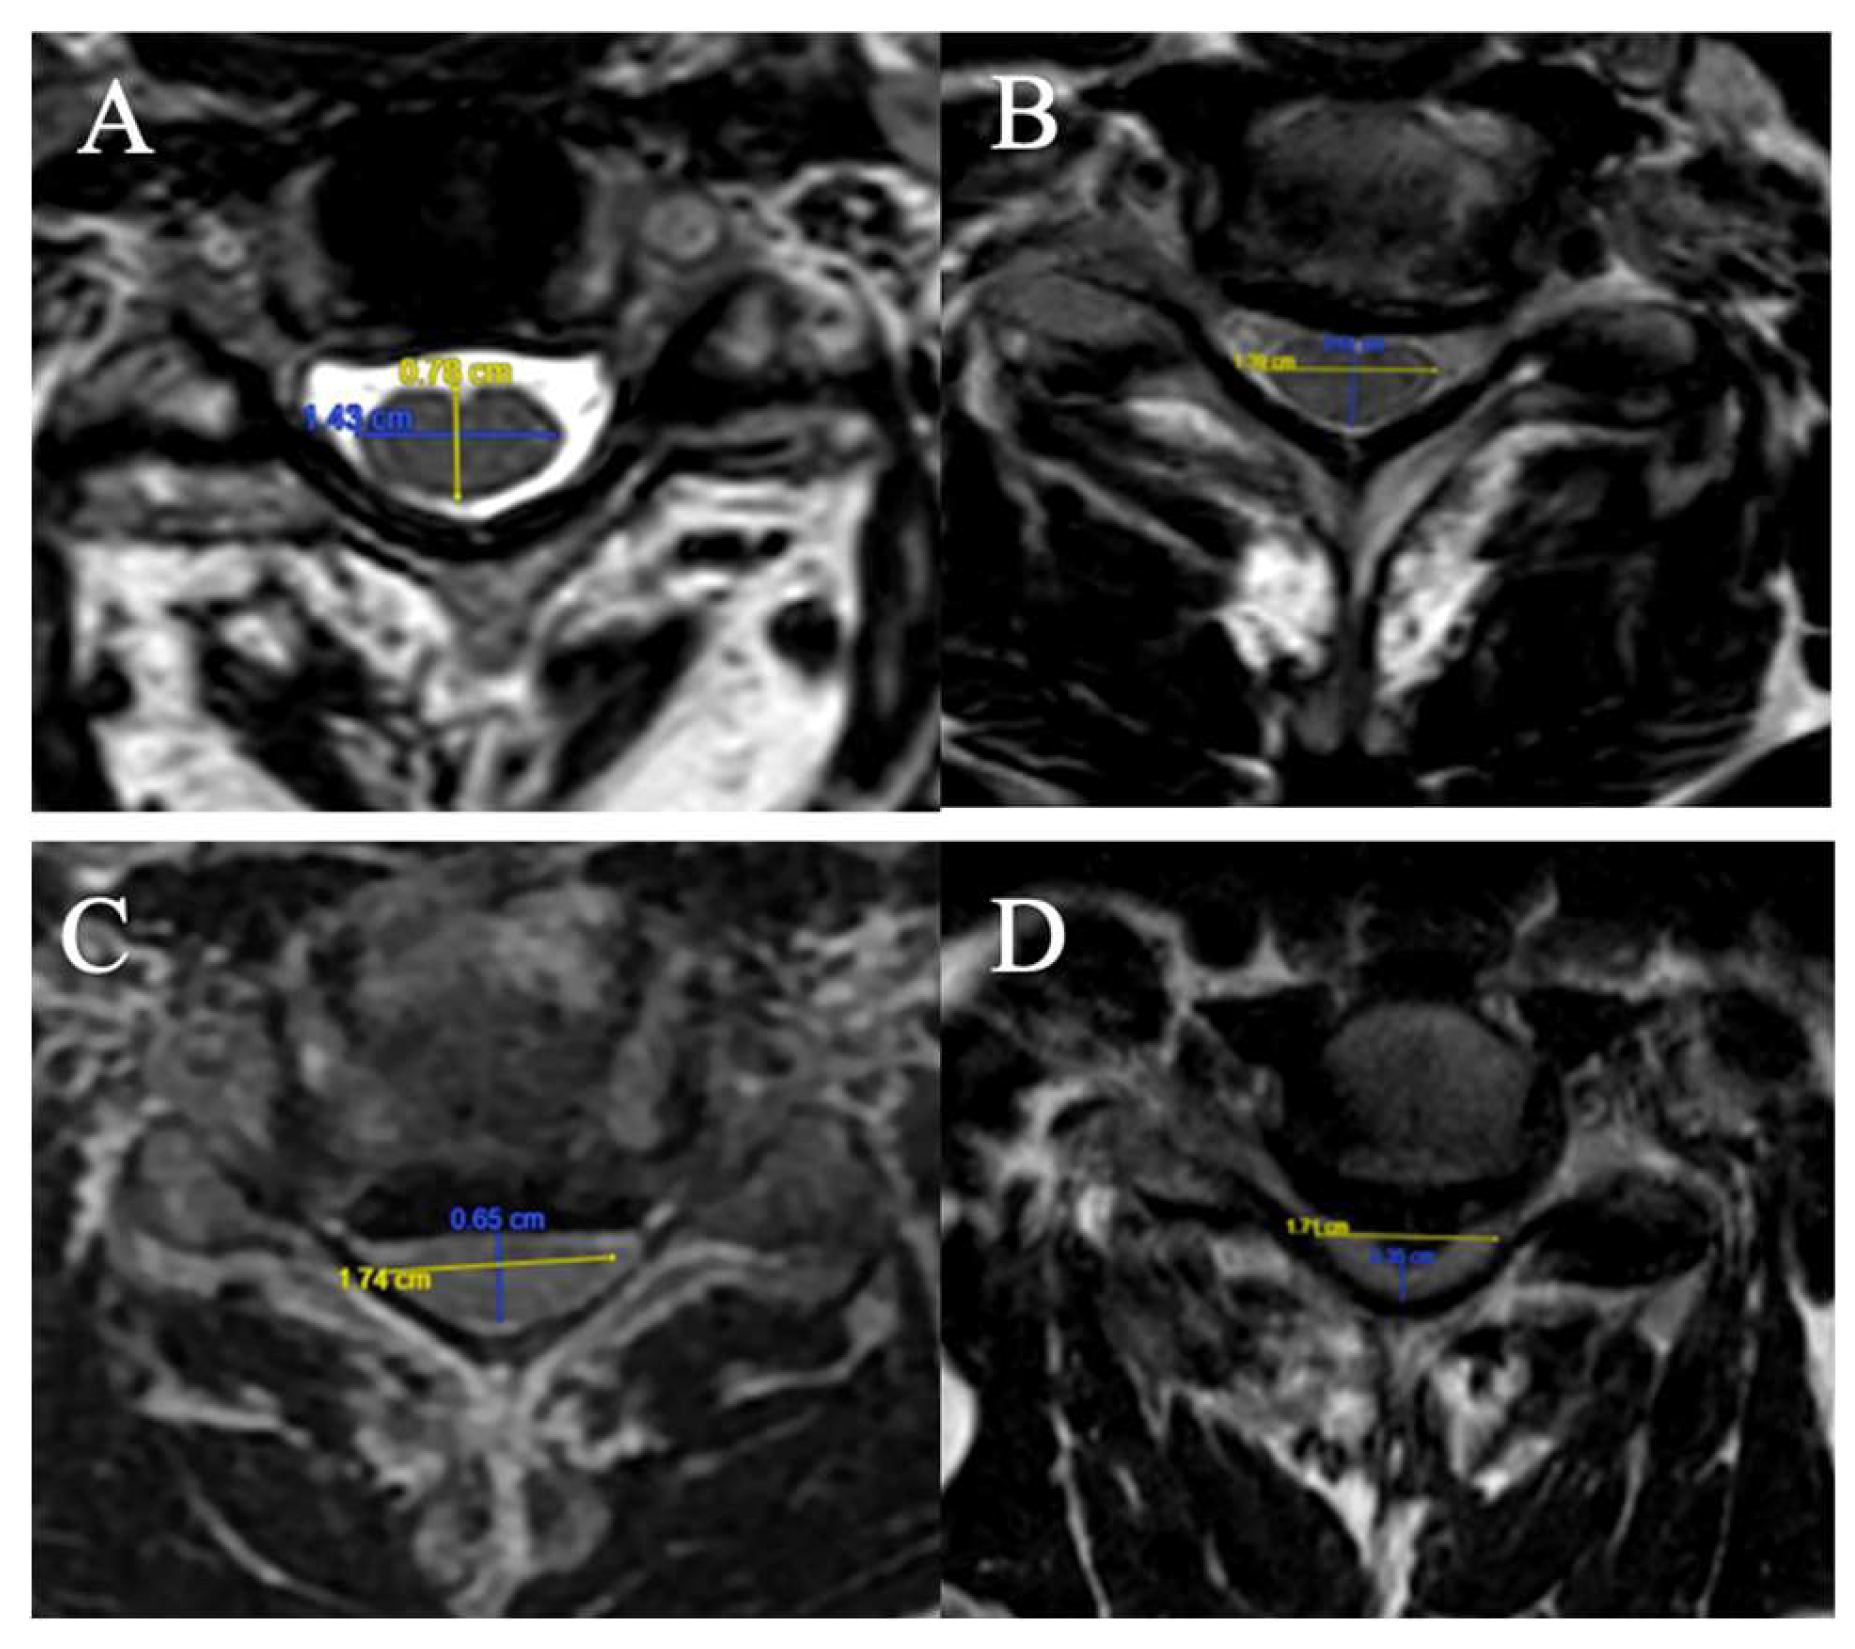

4 grades have been selected on axial slice (Figure 3)

(A) CSF visible anteriorly and posteriorly

(B) CSF erased anteriorly or posteriorly

(C) CSF erased anteriorly and posteriorly but root cisterns still visible

(D) Totally erased cisterns – no CSF visible on the slice

Figure 3. (A): CSF visible anteriorly and posteriorly ; (B) CSF erased anteriorly or posteriorly ; (C) CSF erased anteriorly and posteriorly but root cisterns visible ; (D) Totally erased cisterns.

The FR is defined as the ratio of the anteroposterior diameter of the spinal cord to the transverse diameter on an axial slice at maximum compression on T2-weighted sequences (Figure 1).

Figure 1. FR measured respectively to 0.55 (A), 0.44 (B), 0.37 (C) and 0.20 (D).